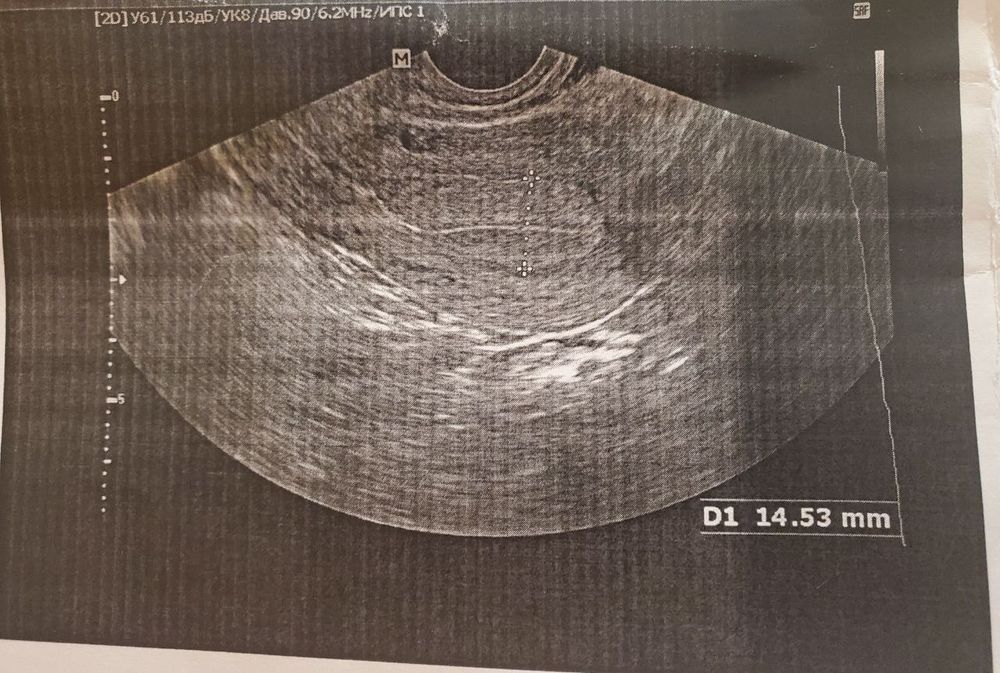

В этот цикл пошла на узи, Запись примерно совпала с днем овуляции по моим подсчетам, За день до О были характерные выделения

На узи мне в итоге сказали что цикл ановуляторный.

Сказала что точно не было овуляции и не будет в этом цикле, и что ей даже не за что "зацепится".

Кто понимает, просмотрите пожалуйста узи, может быть вероятность что О все-таки была но ЭТ просто еще нет? Или оно сразу появляется?

Судя по тому, что фолликулы до 8мм, и эндометрий не соответствуют 2 фазе цыкла - не было.

Там гиперплазия эндометрия 14.5мм.Нету жёлтого тела ( кровотока в нем), жидкости в позадиматочном пространстве.

Inna, тогда жидкость в позадиматочном пространстве должна быть 100%, ее нету. Согласна, желтое тело может не визуализироваться. Хотя нужно надеяться, перед НГ случаются чудеса)

Если бы была овуляция, была бы свободная жидкость, а ее нет.